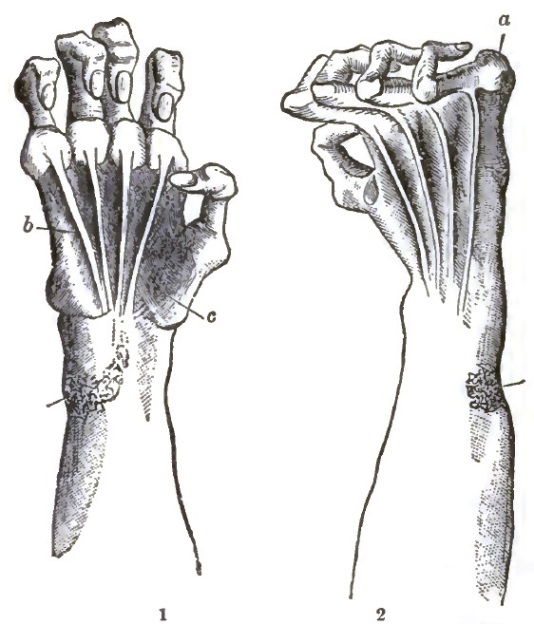

| 32. | DEFORMITY OF HAND IN PROGRESSIVE MUSCULAR ATROPHY |

DELAFIELD, FRANCIS, M.D.,